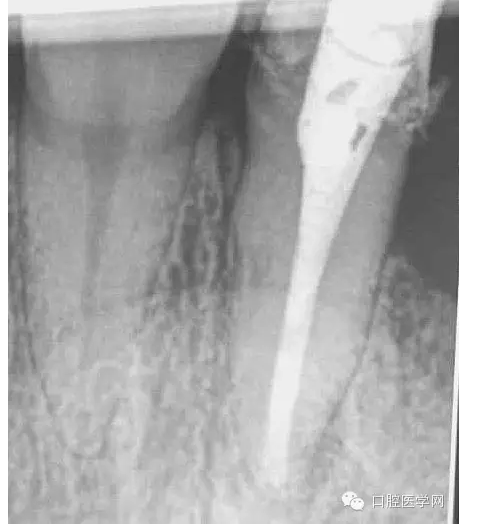

1.先根測(cè)根長(zhǎng),再用機(jī)擴(kuò)對(duì)根管進(jìn)行預(yù)備;

2.用2%次氯酸鈉+2%氯己定+17%EDTA交替沖洗,在用超聲蕩洗。干燥,封氫氧化鈣十天。

3.十天之后復(fù)診,無(wú)明顯癥狀,。準(zhǔn)備再次用2.5%次氯酸鈉+2%氯己定+17%EDTA交替沖洗,在用超聲蕩洗。